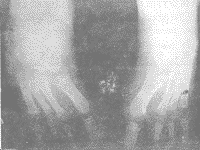

患儿,男,8岁,1990年10月出生,生后发现左手及双足均为4指(趾),且左手3、4指并指,右足内翻畸形。1999年6月来我院就诊。以“左手示指缺如并3、4指并指畸形”入院。检查:发育良好,营养中等,神志清楚,智力正常。头颅及五官正常,心、肺、腹无异常,除左手及双足外,脊柱四肢无畸形,功能正常。左手第2指全指缺如,第3、4指并指。伸屈尚好但肌力Ⅳ级,余指正常。双足第2趾缺如,余趾活动正常。右足内翻畸形,外翻不能,腓骨长短肌肌力0级。X线片示:左手示指掌骨指骨缺如,第3、4指末节骨并联(见图1)。双足第2楔骨及第2跖骨、趾骨缺如(见图2)。右足呈内翻畸形(见图3)。

图2 双足X线片